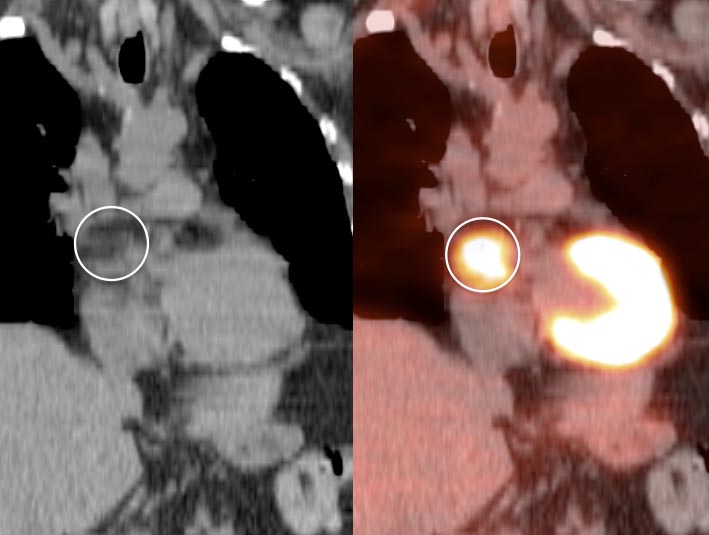

Lipomatous Hypertrophy of the Inter-Atrial Septum

LHIAS is focal fatty infiltration of the inter-atrial septum of the heart. It behaves as hypermetabolic brown fat, and is often intensely FDG-avid, appearing mass-like on the PET images.

Although a non-malignant finding, there are reports of a rare association with arrhythmias.

Diagnosis of this hypermetabolic PET finding is confirmed by the presence of only fat on the co-registered CT images.

Misdiagnosis of this “Aunt Minnie” is unacceptable (as in the terrified patient referred to us from Europe, who flew in with his images to further evaluate his “heart cancer”).

Although benign, we recommend mentioning this finding in the body of the report, as it often looks impressive on the PET images and can prompt a call from a clinician concerned that you “missed” a mass.

We generally report:

“Incidentally noted is lipomatous hypertrophy of the inter-atrial septum, typically of no clinical significance.”